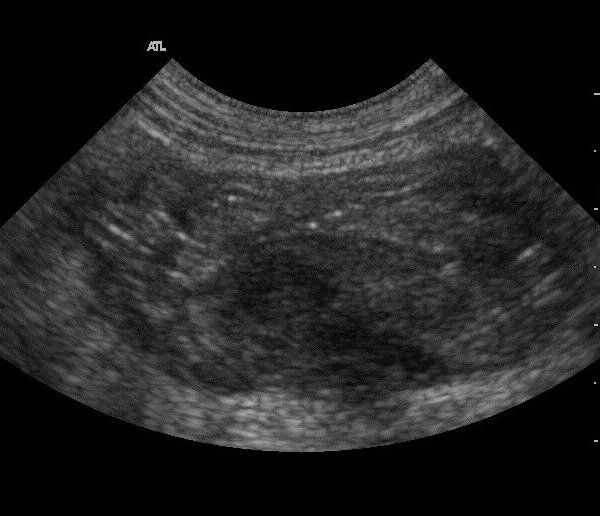

Sonografía

Puede ser diagnóstica por sí misma o un valioso complemento de la radiología.

Además, es una herramienta muy útil en la toma de muestras.